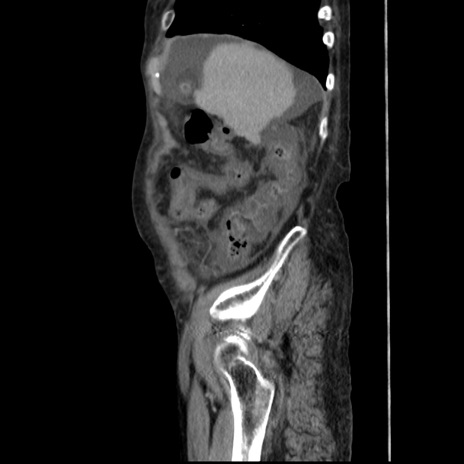

症例31(矢状断像)

【症例】80歳代 女性

【主訴】腹部膨満感

【現病歴】他院にて肝硬変にてフォロー中。1週間前から便秘、腹部膨満感、臍部腫瘤あり受診となる。

【既往歴】肝硬変

【身体所見】腹部膨隆あり、皮膚変化なし、疼痛なし。

【データ】WBC 4600、CRP 0.25